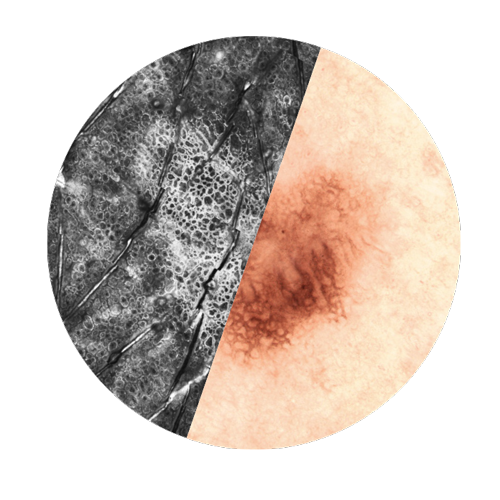

Our In Vivo product line allows for a real-time and non-invasive Instant Optical Biopsy from the epidermis to the upper dermis. With the VivaScope confocal laser scanning microscopy the cell morphology of the skin layers are displayed in high resolution.